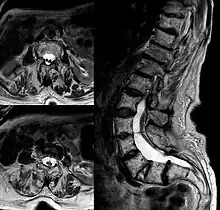

IRM d'une diastématomyélie de la colonne lombaire.

La diastématomyélie est une duplication de la moelle épinière dans le plan sagittal. Un septum osseux ou cartilagineux est volontiers associé à la division médullaire (en son absence on parle de diplomyélie). Ce septum siège habituellement à la face postérieure du corps vertébral et rarement à la face ventrale de l'arc postérieur. Dans la moitié des cas, l'âge de découverte se situe avant 5 ans. Parmi les manifestations cliniques, on retrouve: